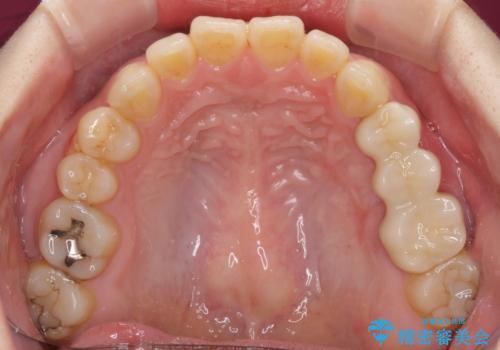

抜歯後に治癒を待って、フルジルコニアブリッジにて補綴することとしました。

抜歯をしたことで、ずっと気になっていた異臭から解放されました。

手前の歯を削ってブリッジ治療とするのか、インプラントによる治療とするのか、悩んでいらっしゃいましたが、奥歯の銀歯もセラミックにしたいとのことで、ブリッジ治療を選択されました。